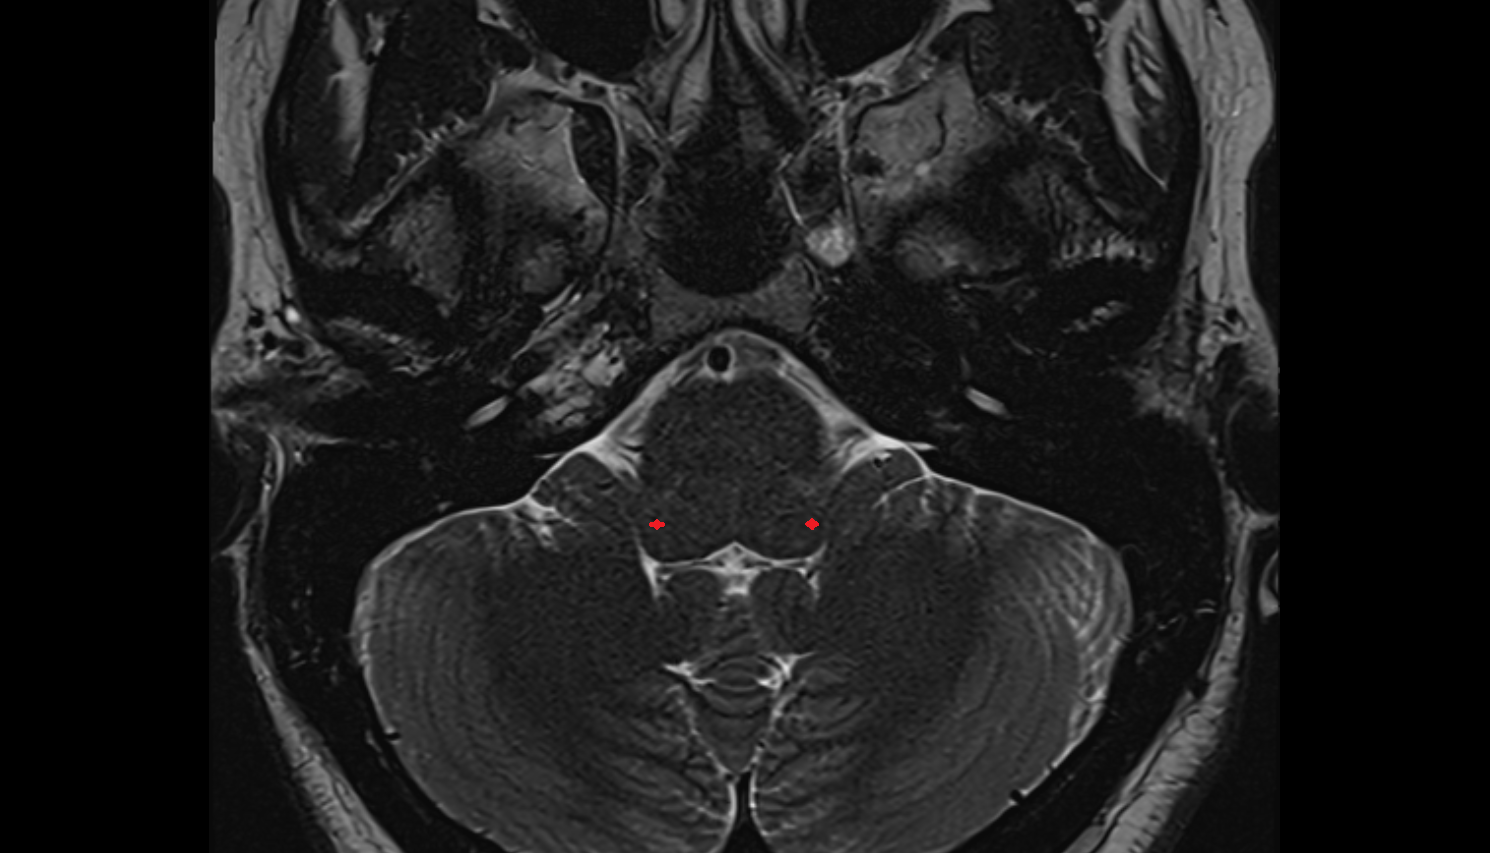

- Cerebellum

- Dentate nucleus

- Middle cerebellar peduncle

- Flocculus

- Crus I of ansiform lobule of cerebellum

- Crus II of ansiform lobule of cerebellum

- Paramedian lobule (HVII) of cerebellum

- Simple lobule (HVI) of cerebellum

- Anterior quadrangular lobule (HV) of cerebellum

- Anterior quadrangular lobule (HlV) of cerebellum

- Biventral lobule (HVIII) of cerebellum

- Cerebellar tonsil (H IX)